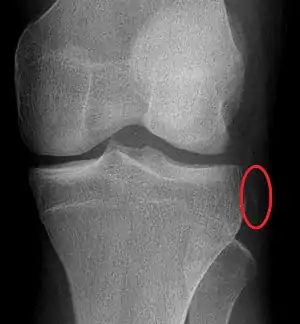

Plain X-rays, CT scan, ultrasonography, or MRI may help with the diagnosis.[2][10] Findings on X-ray that may be useful among those who have already reduced include a variable joint space, subluxation of the joint, or a Segond fracture.[5]

They may be divided into five types: anterior, posterior, lateral, medial, and rotatory.[4] This classification is based on the movement of the tibia with respect to the femur.[10] Anterior dislocations are the most common, followed by posterior dislocations.[2] They may also be classified based on what ligaments are damaged.[2]